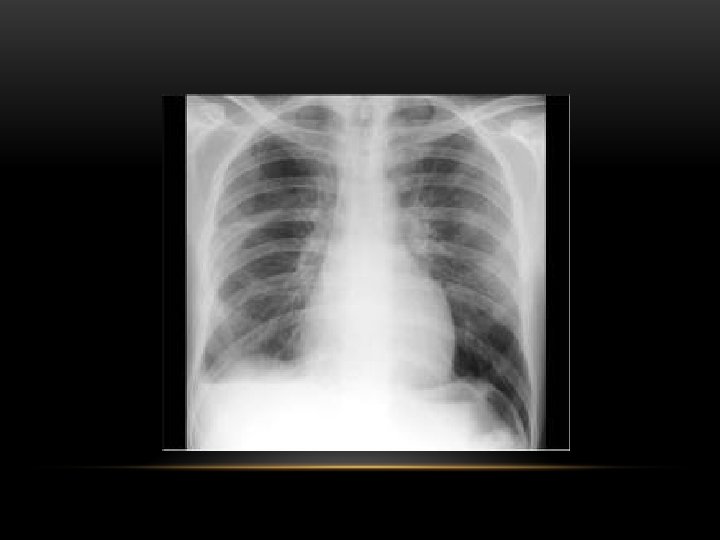

Pneumothorax • No vascular markings on right • No shift of mediastinum to left • Atelectasis right lung • Increased haziness on left: Diversion of entire cardiac output • Small fluid level near costophrenic angle: Hydro pneumothorax

Spontaneous Pneumothorax • Air in pleural space • Lung margin • "Normal lungs": Note the radiolucency of atelectatic lung is the same as the opposite lung